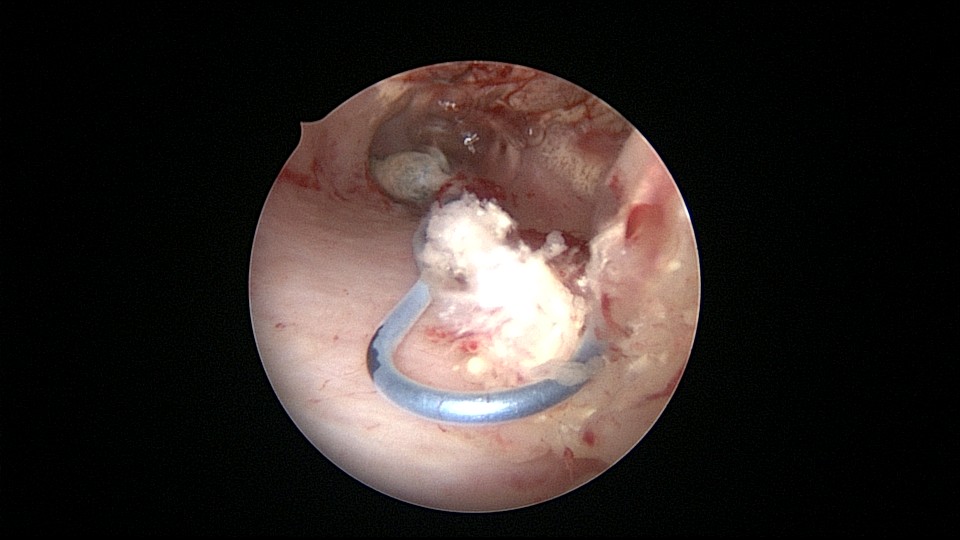

患者55岁,G4P1,顺产1次。安环16年,绝经5年,外院取环失败。子宫前位,宫颈萎缩,宫腔下段左后壁见假道,假道内见肌瘤结节突出,爱母环位置正常,宫腔左侧壁及前壁见占位质脆组织,表面有异常粗大血管。异物钳顺利取出节育环,占位组织病检为内膜样癌。取环造成的假道让病人因祸得福,提前发现了子宫内膜样癌,得以及时手术治疗。